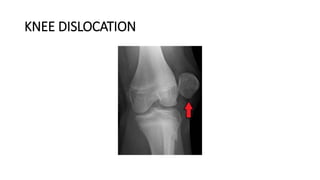

KNEE DISLOCATION

• Knee dislocations are ligamentous disruptions with loss of continuity of

tibiofemoral articulation.

• A combination of tears of the anterior cruciate ligament (ACL), posterior

cruciate ligament (PCL), medial collateral ligament (MCL), lateral collateral

ligament (LCL), and other stabilizing structures are typical of knee

dislocations.

• The vast majority of knee dislocations involve disruption of both the ACL

and PCL.

• Anterior displacement is considered the most common type of knee dislocation.

• The least common type is the posterolateral dislocation.

• They most commonly occur from high-energy mechanisms (motor-vehicle

wrecks, industrial accidents), but they can also occur from low-energy trauma

(sporting activities and minor falls).

• In the absence of vascular and open injuries, treatment options include

nonsurgical and surgical management options.